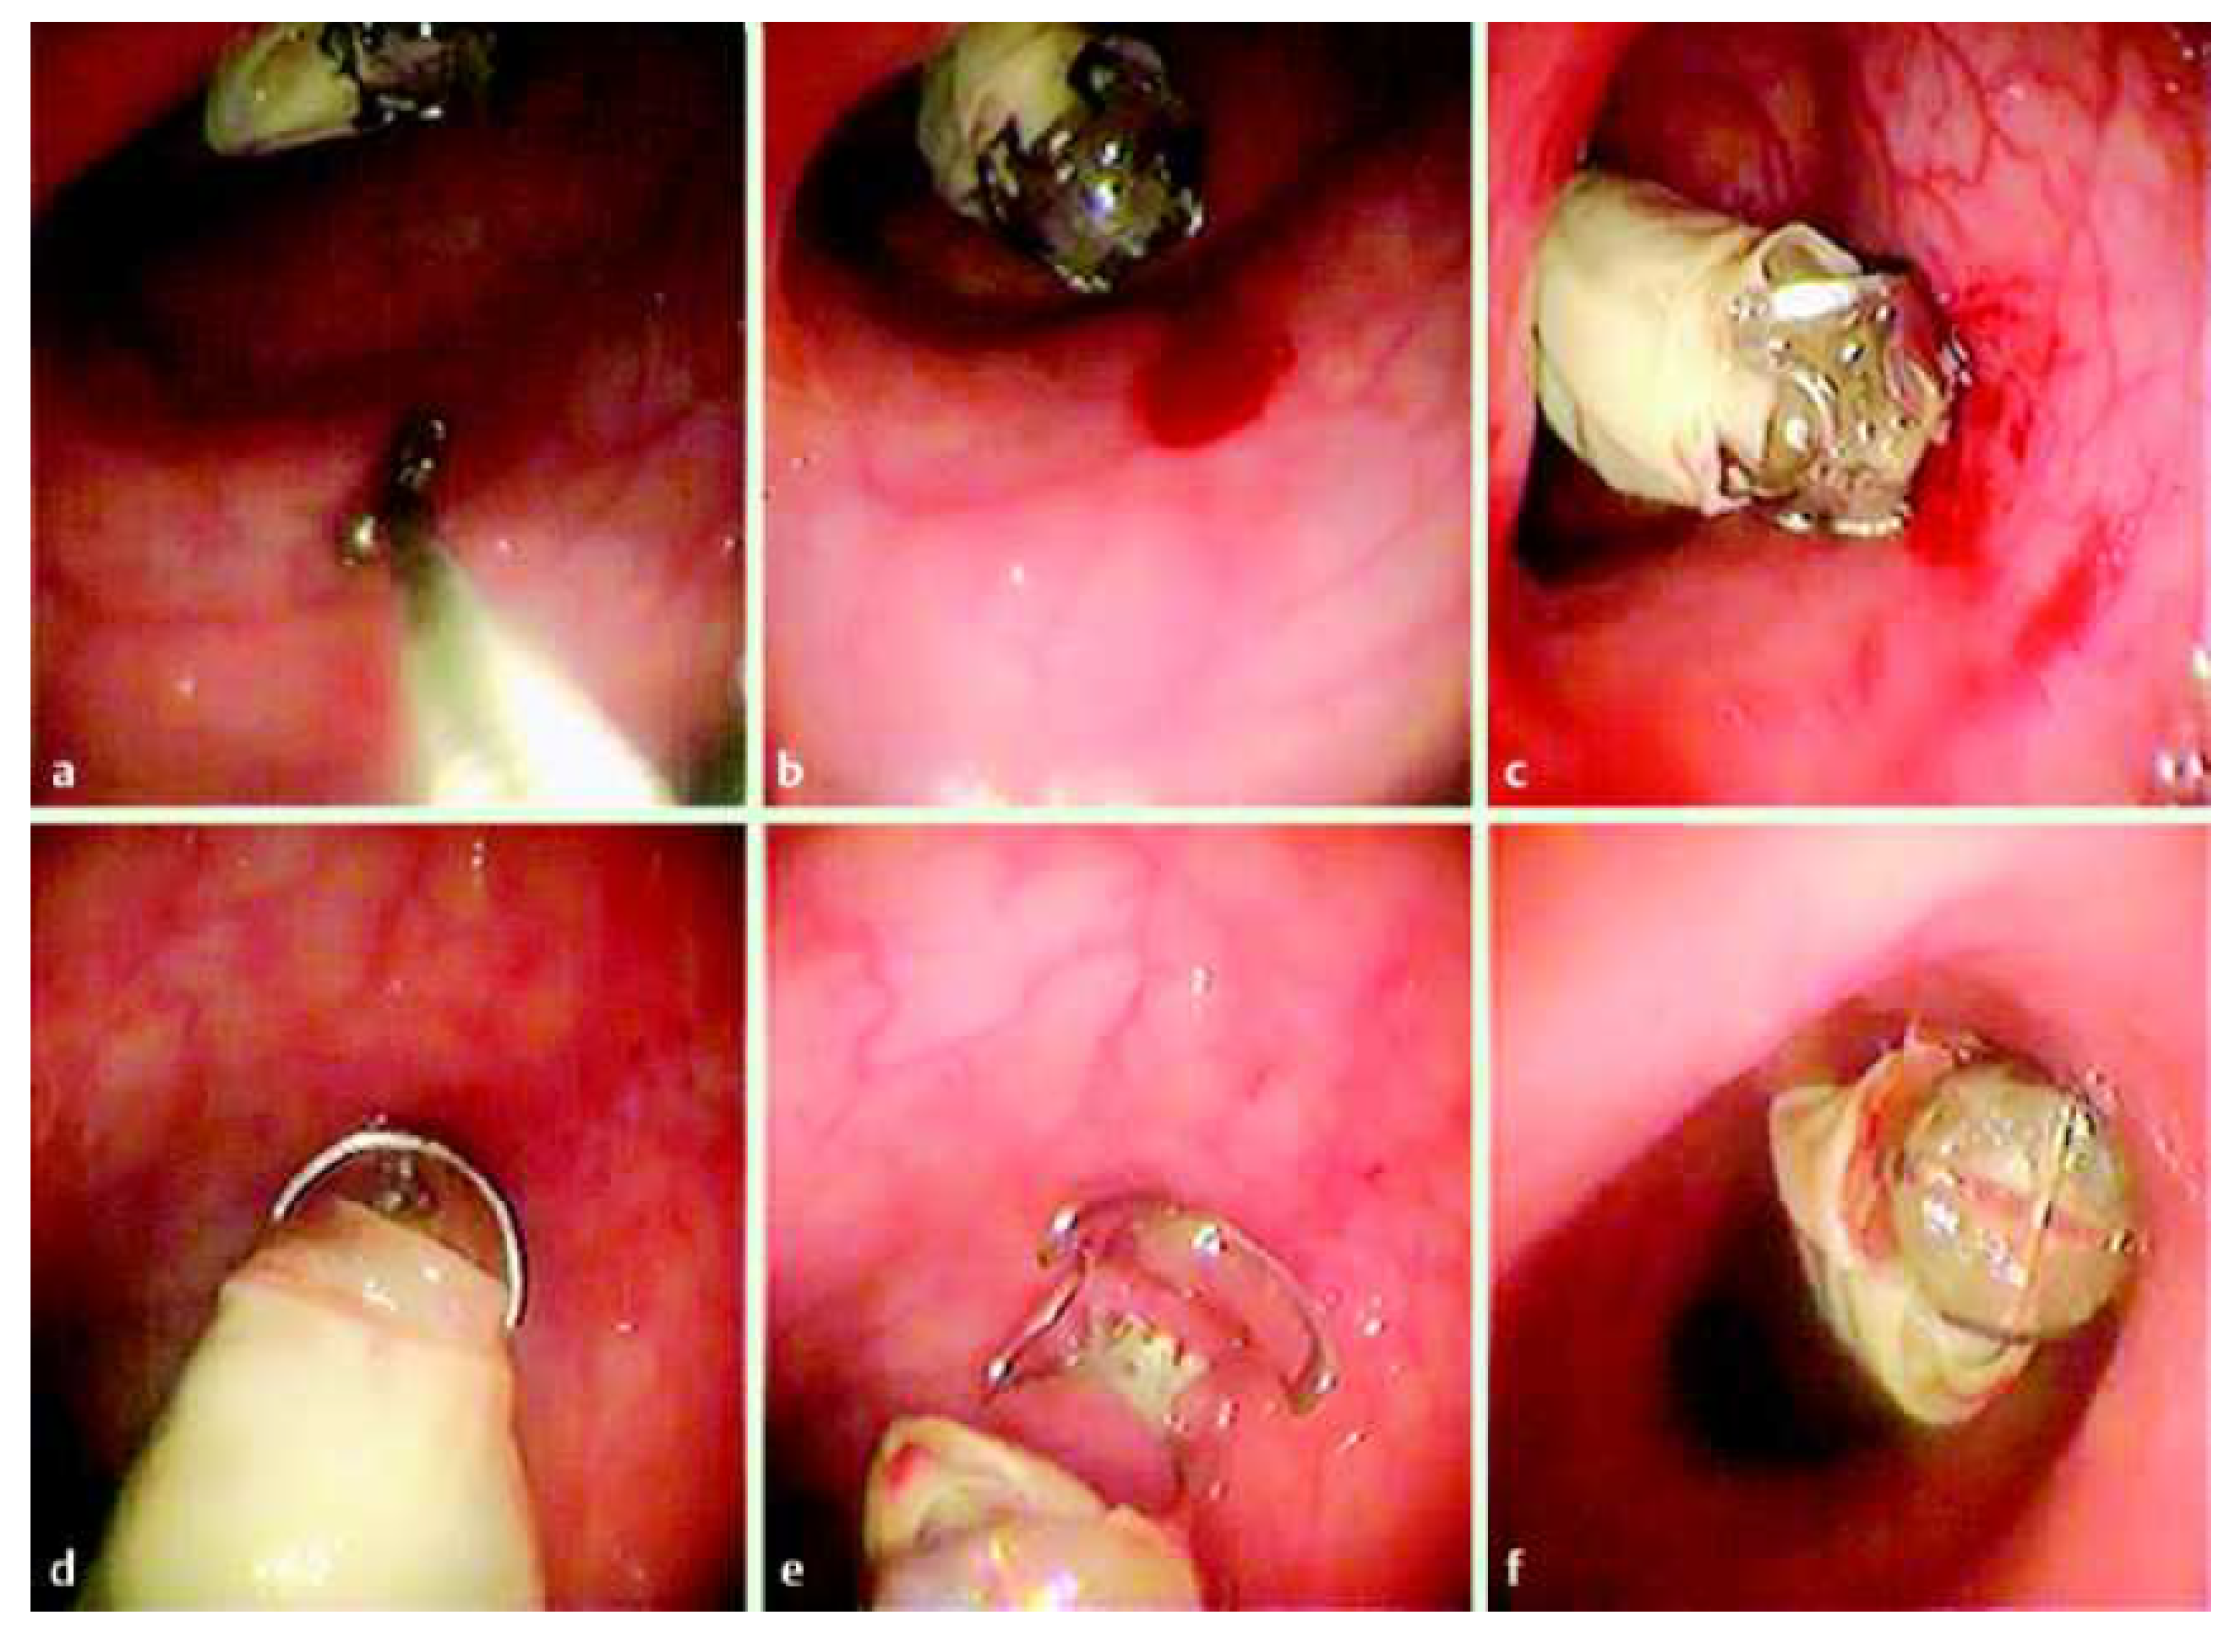

6.2. Hemostasis

7. Retention